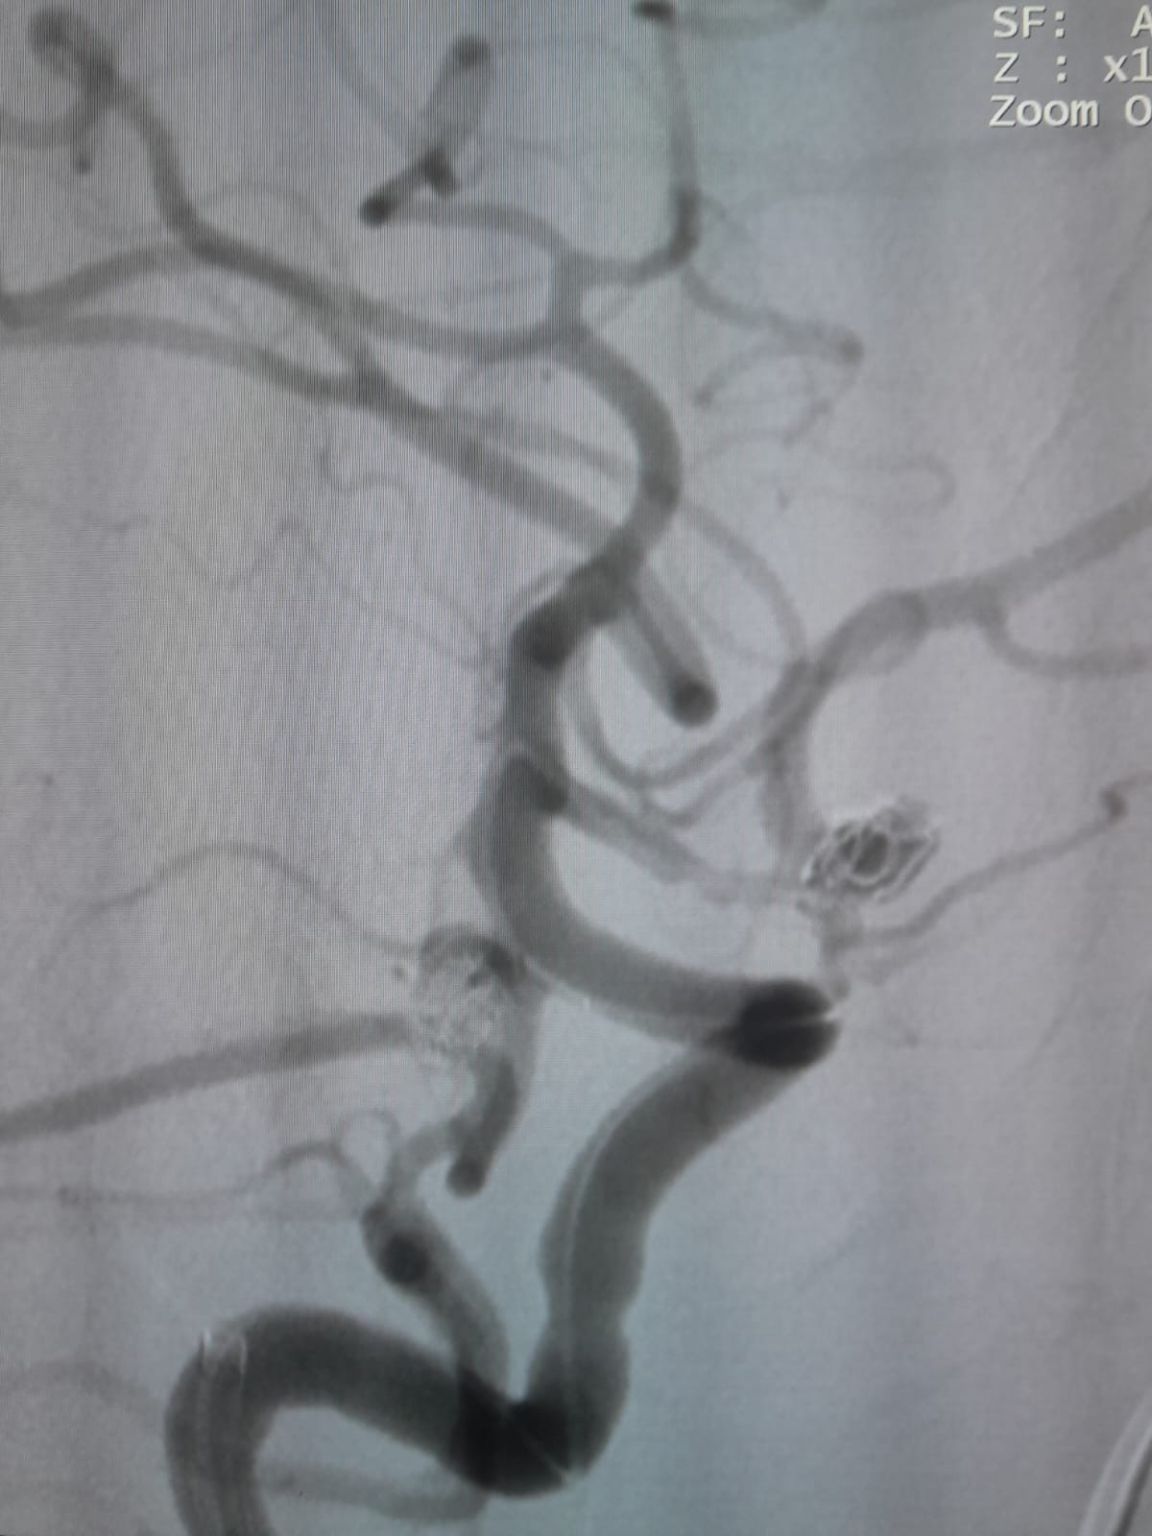

O acesso vascular foi estabelecido e a equipe então navegou com sucesso o Frepass®Microcateter descartável (TJMC14) para o local alvo. Embolização foi realizada utilizando três Perdenser®Embolic Coil System (TJCST4.508-3D, TJCST0306-3D, TJCST0206-3D) implantado com o Deromper®Bobina destacamento controlador (TJCDC).

Aneurisma Comunicando Artéria Posterior (Re-tratamento)

Durante o acompanhamento, observou-se enchimento residual no aneurisma da artéria comunicante posterior previamente tratado. A equipe acessou novamente o site usando o Frepass®Microcateter descartável (TJMC18 Plus) e implantado com sucesso um Nuva®Desvio do fluxo (TJED-D-4.5-16), que demonstrou a aposição ideal da parede e o desvio excelente do fluxo, conduzindo aos resultados altamente satisfatórios do tratamento.